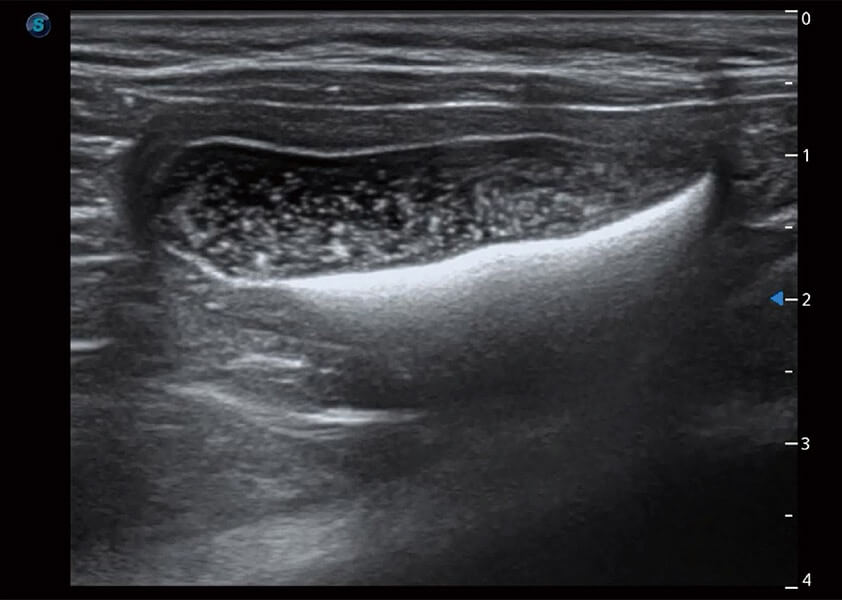

优异的基础图像

(猫)膀胱结晶